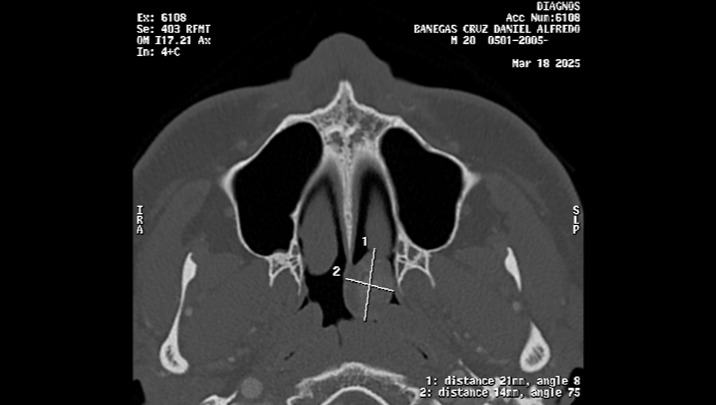

As some of you are already aware, my son Daniel Alfredo (20 years old), is about to undergo urgent surgery due to a (benign) Nasopharyngeal Angiofibroma tumor (in the upper area of the throat, behind the nose), and the medical expenses are quite high, around $8,000.00, which covers hospitalization, medical fees, medications, studies prior to surgery, and transfusions (if needed).